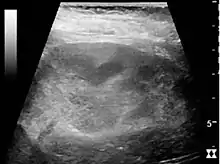

Ultrasound findings that indicate pyelonephritis are enlargement of the kidney, edema in the renal sinus or parenchyma, bleeding, loss of corticomedullary differentiation, abscess formation, or an areas of poor blood flow on doppler ultrasound.[21] However, ultrasound findings are seen in only 20% to 24% of people with pyelonephritis.[21]

Chronic pyelonephritis with reduced kidney size and focal cortical thinning. Measurement of kidney length on the US image is illustrated by ‘+’ and a dashed line.[20]